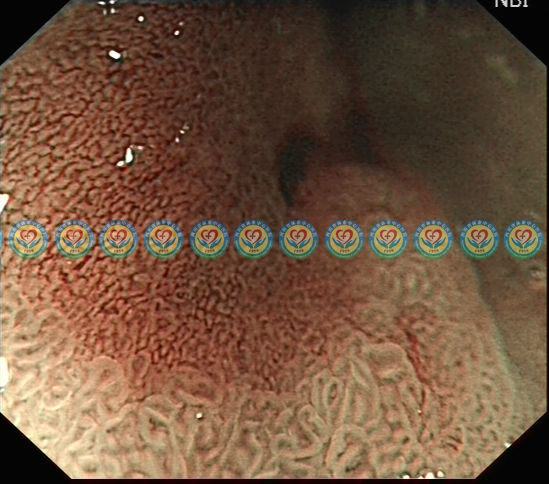

NBI放大观察,病灶呈茶褐色,与周围正常粘膜存在明显边界线